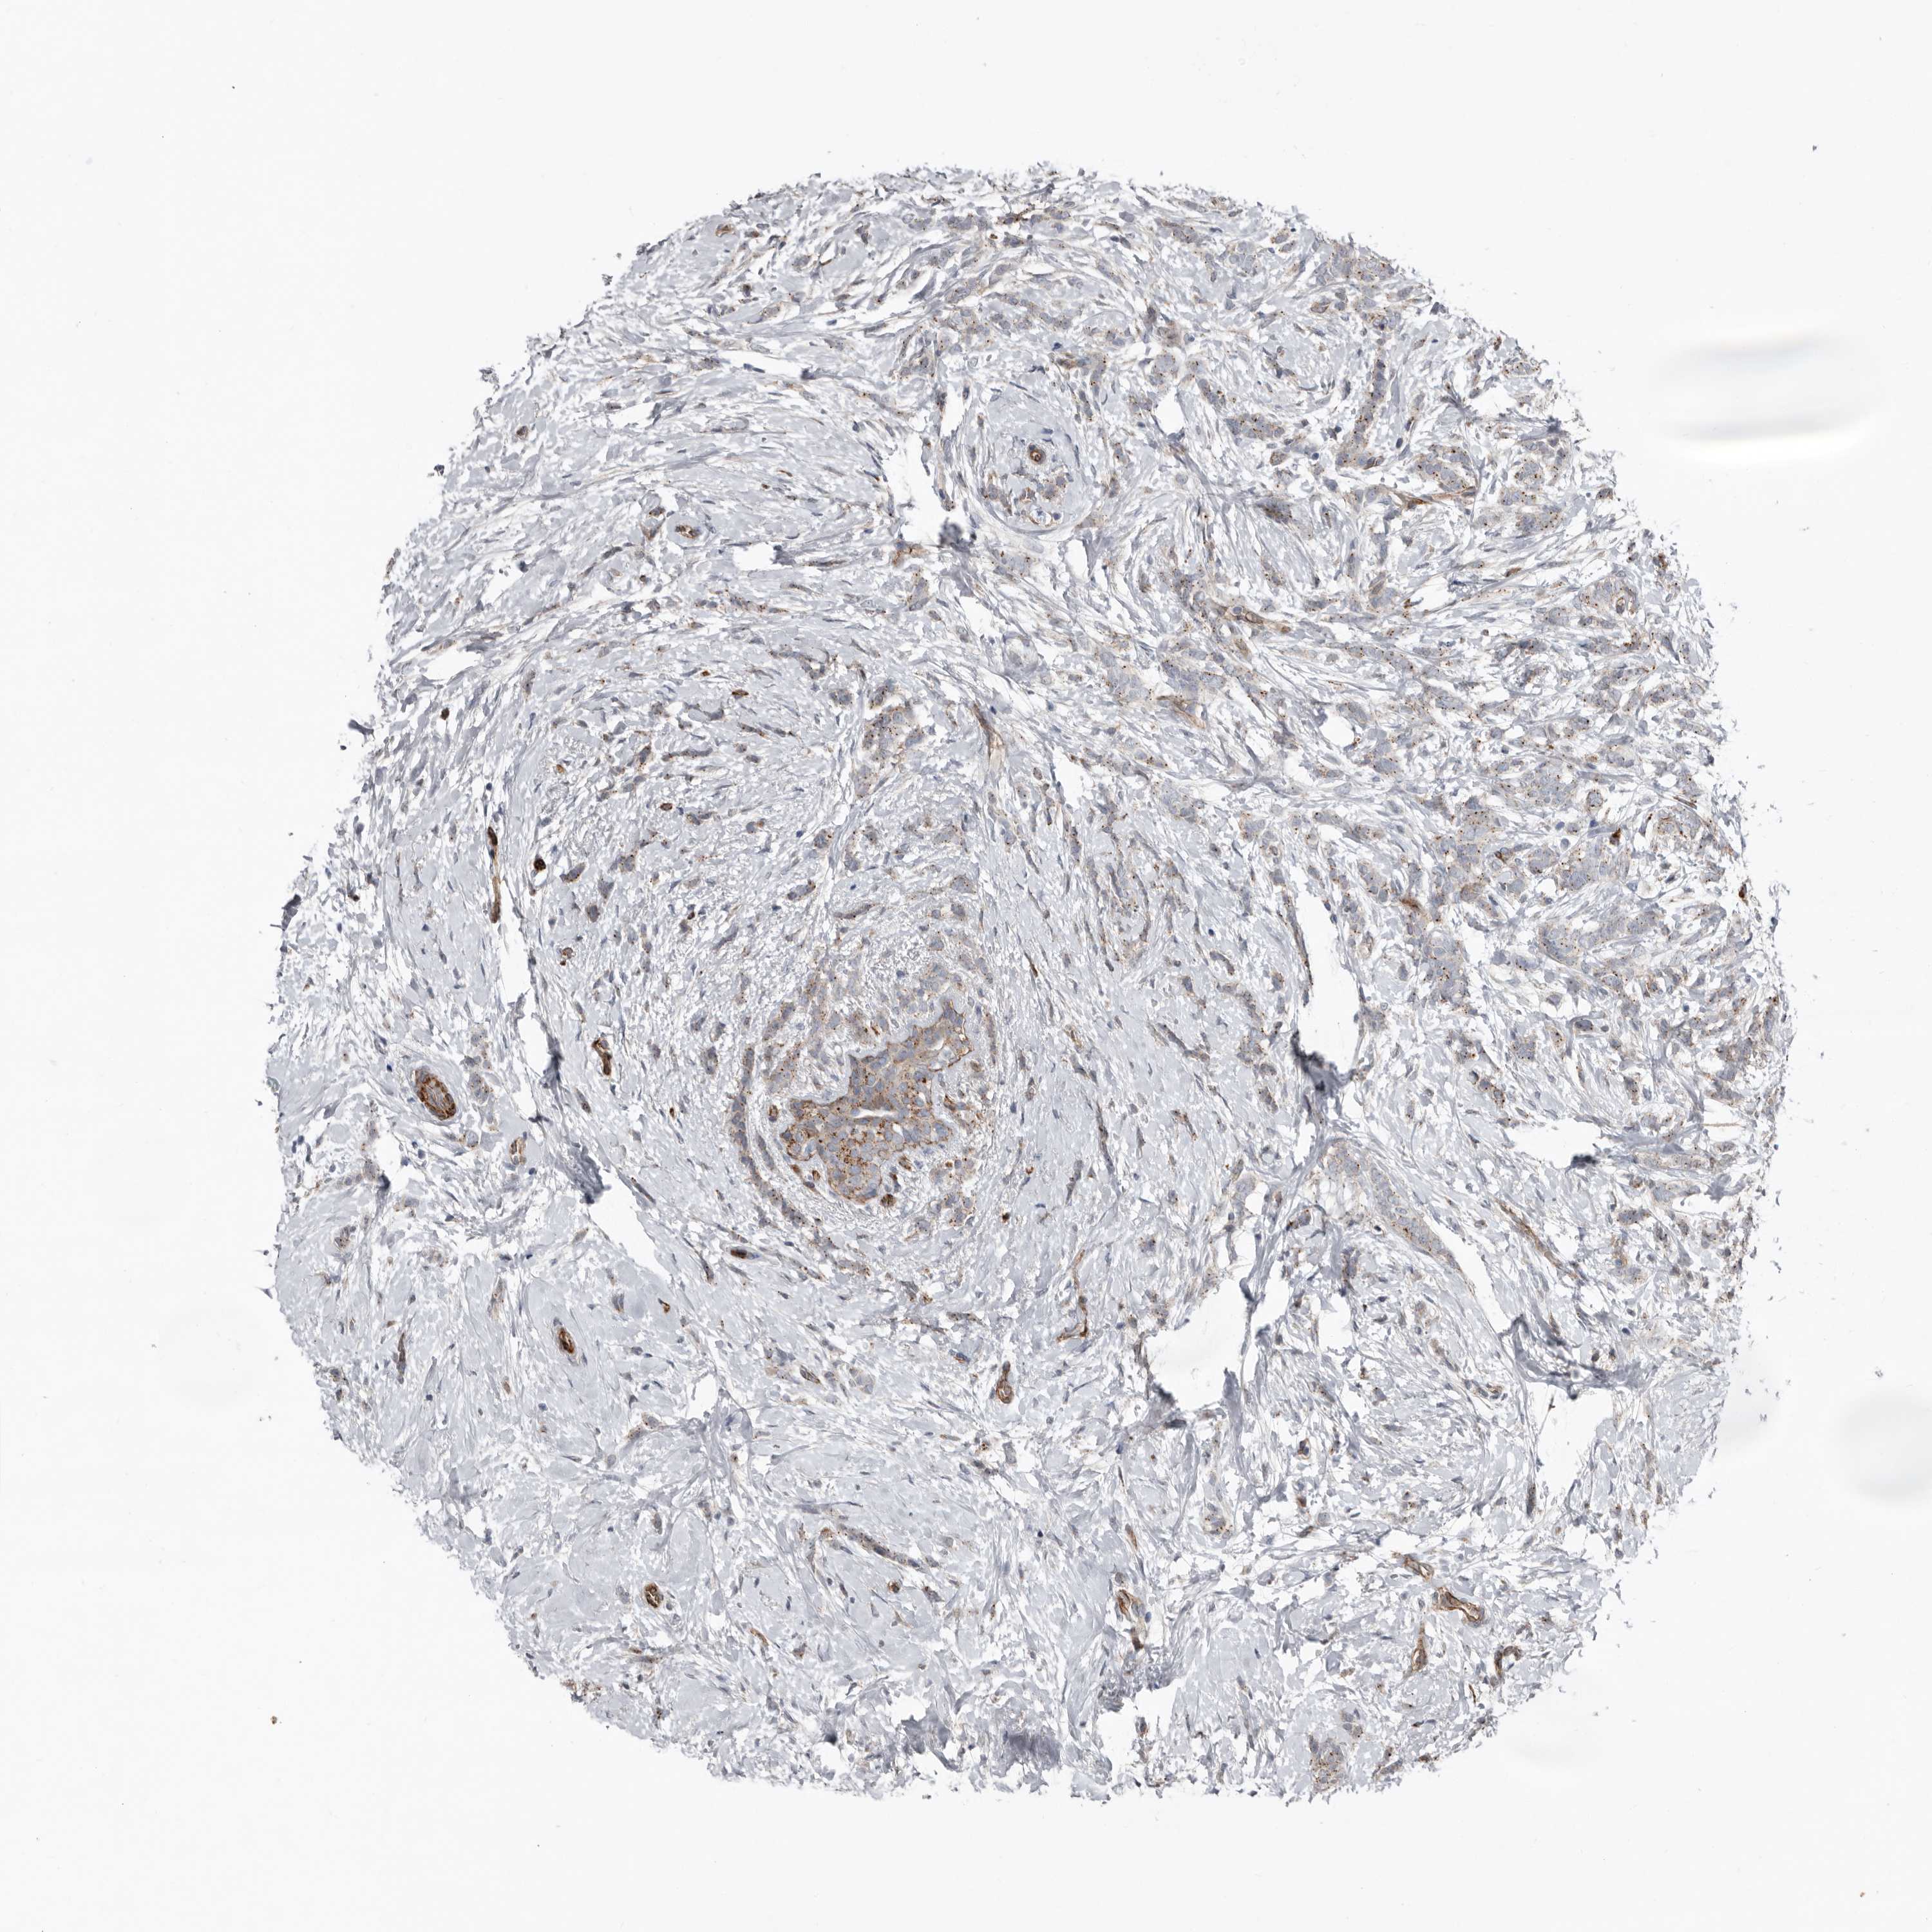

CANCER BREAST CANCER Show tissue menu

BRCA TCGA BRCA VALIDATION PROTEIN EXPRESSION